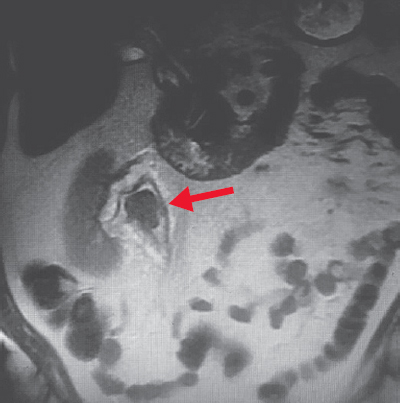

По данным патогистологического исследования удаленная опухоль лоханки представляла собой мышечно-неинвазивную уротелиальную карциному high-grade (стадия pT1NoMo). Учитывая отсутствие контралатеральной почки, адъювантную химиотерапию не проводили. При контрольном обследовании в 2021 г. у пациента по данным мультиспиральной компьютерной томографии выявлен рецидив опухоли полостной системы правой почки, на этот раз опухоль размером до 3 см была локализована в проекции верхних групп чашек (рис. 6).

Рис. 6. Компьютерная томограмма сагиттального среза правой почки с опухолью (стрелка), в проекции верхних групп чашек

Fig. 6. Computed tomogram of the sagittal section of the right kidney with tumor (arrow), in the projection of the upper groups of calyces

Принято решение о повторном оперативном лечении перкутанным доступом. В положении пациента на животе под эндотрахеальным наркозом выполнена пункция полостной системы правой почки через нижнюю группу чашек, пункционный тракт бужирован до 24 Ch и установлен кожух Амплатц. С помощью гибкого видеонефроскопа произведена ревизия полостной системы правой почки, в проекции зоны предыдущей резекции опухоли отмечается рубцово-измененная стенка лоханки, в области рубца рецидива новообразования не выявлено. При дальнейшей ревизии полостной системы правой почки в проекции верхних групп чашек выявлена крупная опухоль крупноворсинчатой структуры на широком основании (рис. 7). Выполнить ее резекцию не представлялось возможным из-за острого угла «атаки» и невозможности адекватно провести инструмент в верхнюю группу чашек. Принято решение о применении дополнительного перкутанного доступа в проекции верхних групп чашек. Под ультразвуковым и визуальным контролем прецизионно был произведен второй доступ в верхнюю группу чашек вблизи с новообразованием (рис. 8).